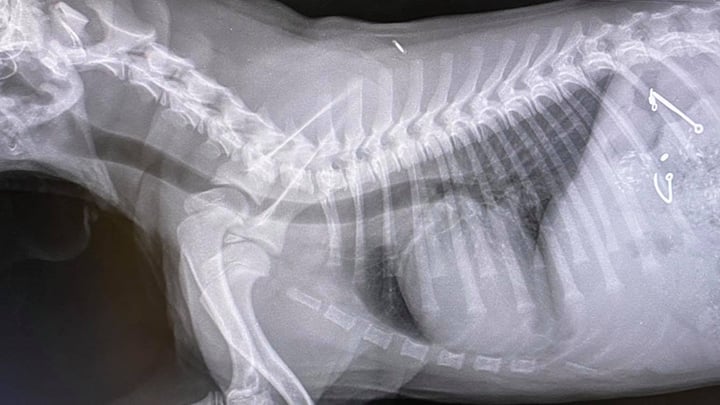

The Sutton Farm team took him in to get some x-rays and could see not one but two fish hooks in his stomach. Branch Partner and Veterinary Surgeon, Emma advised his owner that, given their nature and ability to do serious damage to his stomach, they needed to perform emergency surgery.

Barney was immediately taken to theatre where his abdomen was opened, and a small incision was made into his stomach. To their surprise, not only did they find the fish hooks, but Barney had also managed to swallow some fishing floats. Thankfully, the team managed to remove the fish hooks and floats from his stomach and patched him up.